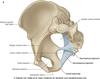

How does the V3 - mandibular branch of trigeminal nerve leave the skull?

Through the sphenoid bone at the foramen ovale

How does V2 - maxillary branch of trigeminal leave the skull?

Through the sphenoid bona via the foramen rotundum